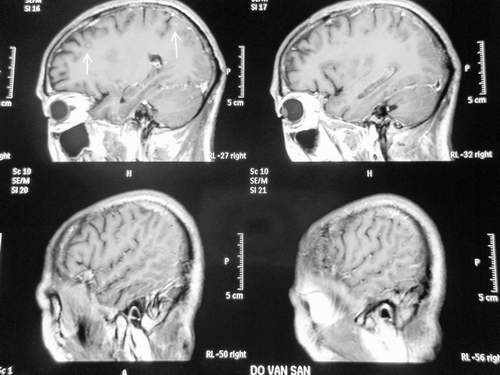

Đó là bệnh nhân nam (53 tuổi, ở Lộc An, Nam Định) làm nông nghiệp, không có tiền sử HIV hay các bệnh lý mạn tính khác. Bệnh nhân có biểu hiện sốt kéo dài nhiều ngày kèm theo gầy sút cân (12kg), ho khan, đau đầu, nôn, chân phù. Đặc biệt, biểu hiện nổi bật là các triệu chứng trên hệ thần kinh, lúc đầu là đau đầu, nôn, sau đó có giảm trí nhớ, liệt nửa người trái, rối loạn tâm thần, co giật động kinh và giai đoạn sau là rối loạn ý thức, hôn mê.

| Hình ảnh nấm não trên MRI (T2). |

Đặc điểm lâm sàng chung của nấm não-màng não là đau đầu, buôn nôn, nôn, rối loạn tâm thần, co giật động kinh, có thể có liệt, hội chứng màng não, rối loạn ý thức, hôn mê. Chẩn đoán xác định nấm P. marneffei trước đây dựa vào soi nấm trực tiếp, nuôi cấy. Trong những năm gần đây đang phát triển kỹ thuật chẩn đoán sinh học phân tử là CPR và giải mã gen với độ nhạy và độ đặc hiệu cao.

Trên bệnh nhân diễn biến lâm sàng ban đầu là hội chứng nhiễm khuẩn nhẹ, sau đó xuất hiện các triệu chứng về hô hấp, suy thận và viêm não; xét nghiệm cùng thời điểm thấy tổn thương ở phổi, suy thận, thay đổi dịch não tủy, nhiễm nấm máu và nấm trong dịch não tủy. Như vậy, bệnh nhân đã bị nhiễm nấm máu, từ đó nấm lan rộng khắp cơ thể và xâm nhập vào hệ thần kinh trung ương.